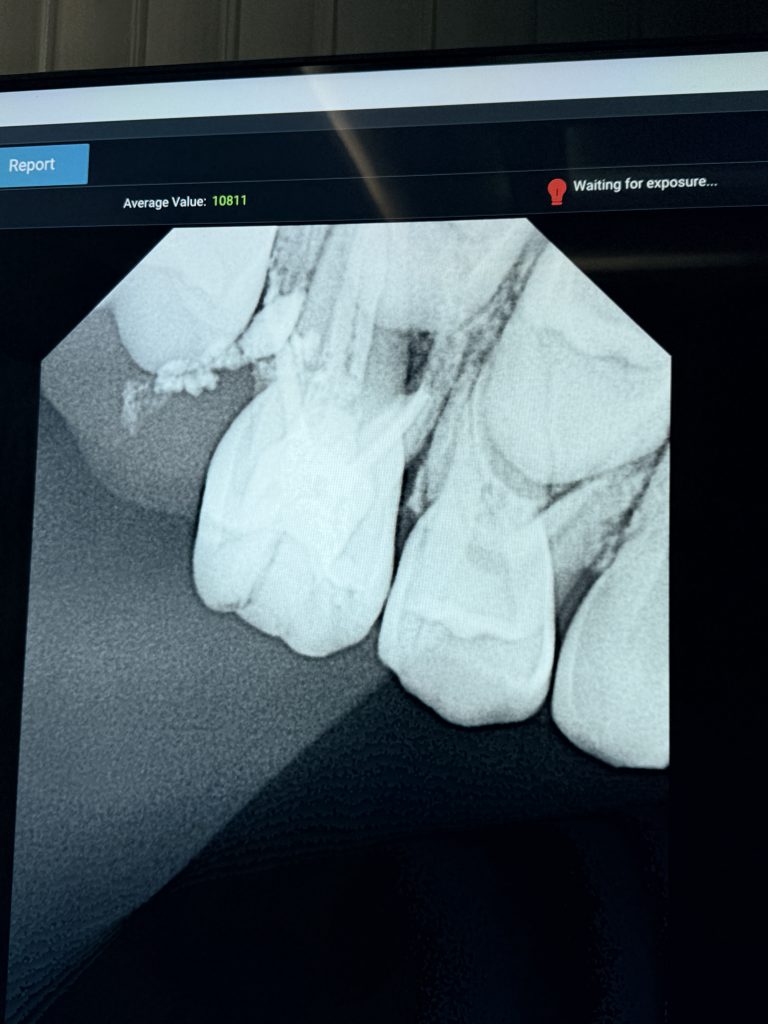

Final radiograph confirmed dense obturation and intact apical seal (Fig 6). At 1-month review, tooth remained asymptomatic, with functional occlusion and healthy periradicular tissues.

- Fig 6: Post-operative radiograph confirming complete fill and apical seal.